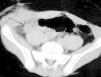

Se presenta el caso de un niño de 13 años que acude a urgencias con un cuadro de dolor en fosa ilíaca derecha y fiebre en las últimas 36 h. Como antecedente de interés destaca una intervención de apendicitis aguda mediante laparotomía hace un año. La ecografía abdominal muestra una estructura quística alargada en fosa ilíaca derecha, de aproximadamente 10 mm de diámetro, junto con una mínima cantidad de líquido libre (fig. 1). En la TC se apreciaban importantes cambios inflamatorios a nivel de fosa ilíaca derecha que se extendían hasta la pared abdominal anterior (fig. 2).

Figura 1. Ecografía de la fosa ilíaca derecha donde se observa una imagen quística tubular.